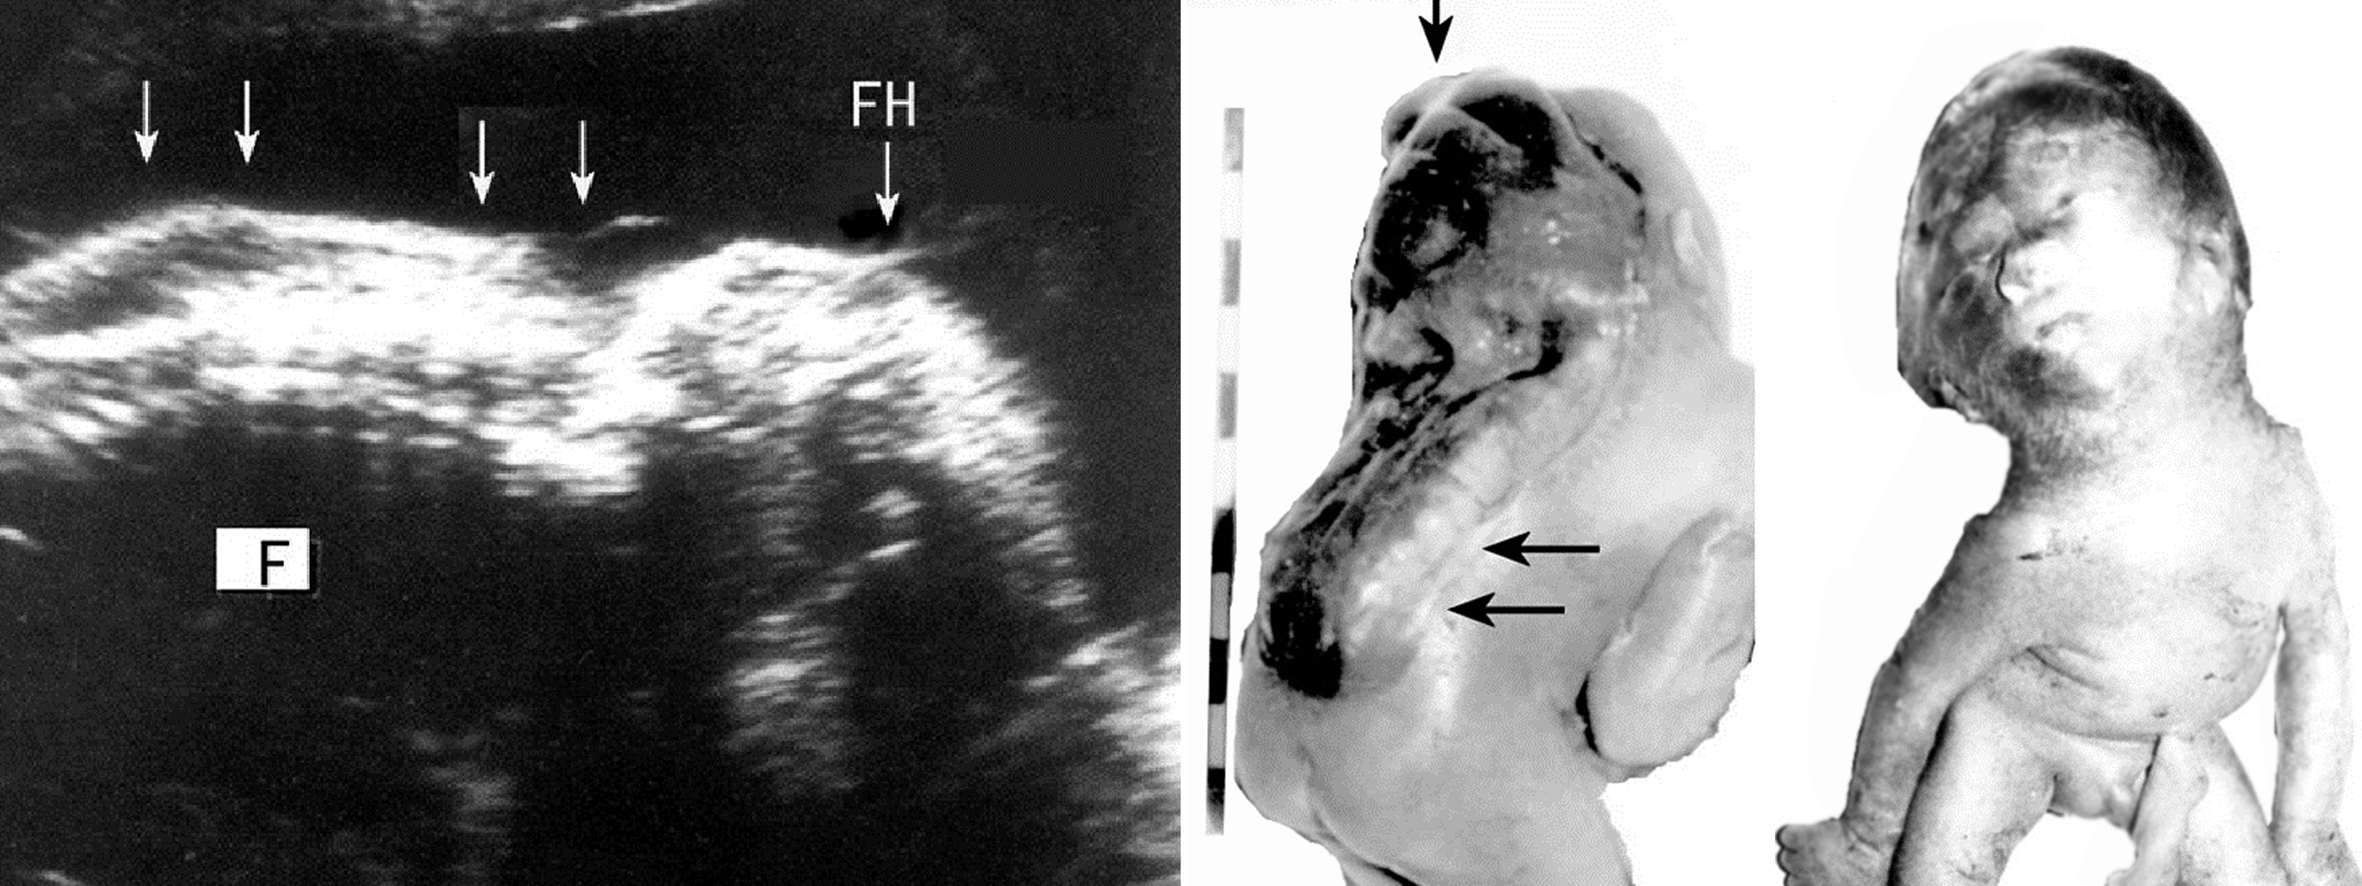

除合并其他部位和器官的异常,如脑积水、无脑儿、心血管系统、泌尿系统和肢体等多种畸形外,脊柱裂也可以有不同种类的复杂畸形,形成复杂性脊柱裂。合并的畸形包括脊髓纵裂、颅裂(图6)、脂肪瘤、神经管原肠囊肿以及脊髓栓系综合征(TCS)等。

图6 脊髓纵裂并颅裂畸形声像图(左)及标本(右)